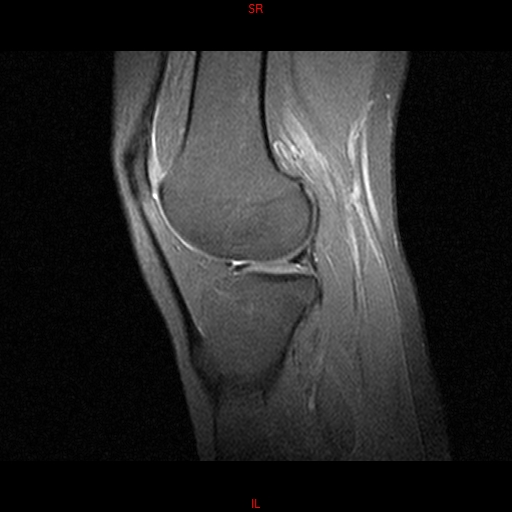

• RESONANCIA PATOLÓGICA MENISCOPATIA INTERNA DP SAGITAL